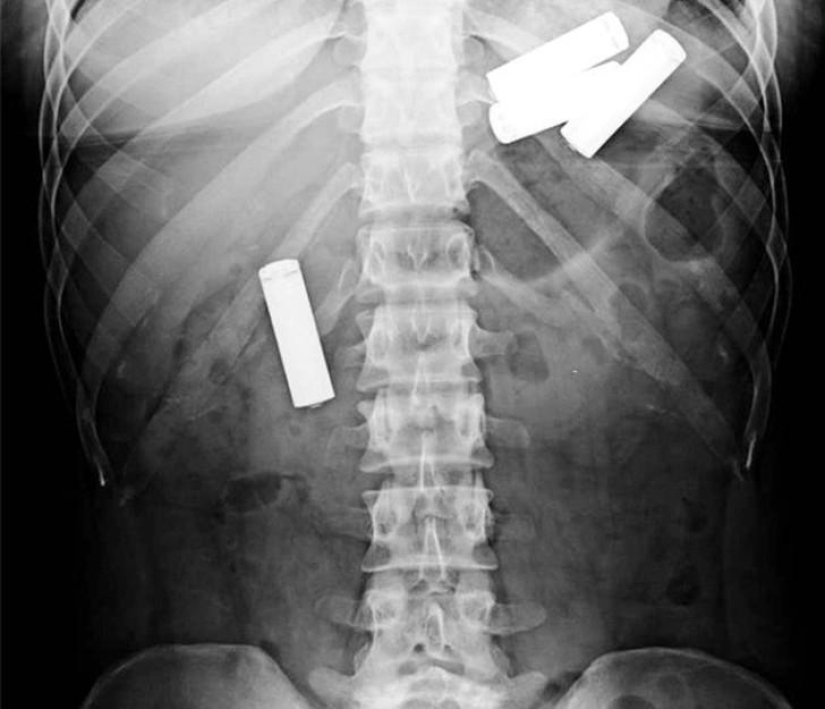

Forceps.